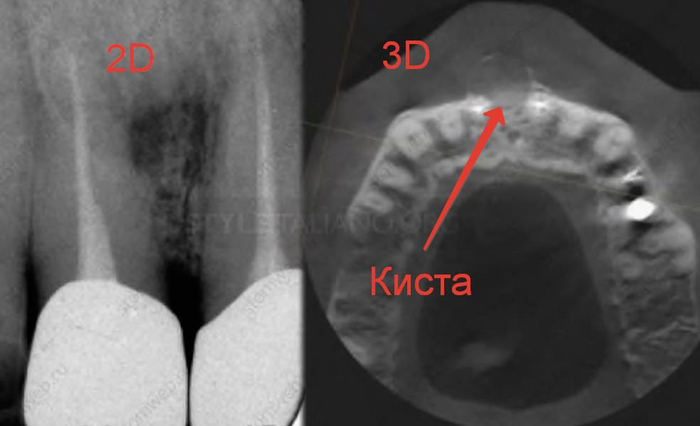

После того, как пациент сделает нормальный трехмерный снимок, с вероятностью 90% мы будем наблюдать один из подобных примеров.

Как вы уже догадались при получении двухмерного изображения трехмерного объекта, его структуры будут накладываться друг на друга. Так как рентген-диагностика заключается в анализе разницы плотности слоев, что выражается на снимках в виде различных оттенков серого, то более плотные слои(белые) могут запросто перекрывать менее плотные(черные), из-за чего точность этой диагностики снижается.

Компьютерная томография «нарезает» объект послойно, позволяя увидеть все структуры под каким угодно углом без искажений. Таким образом мы сможет поставить максимально точный диагноз, определить более точный прогноз зуба, определить расположение будущих и уже установленных имплантатов, определить расположение гайморовой пазухи и нижнего альвеолярного нерва при удалении сложных зубов, определить расположение корней, определить количество каналов в корнях….можно продолжать долго.

Вот ещё примеры.

Поэтому если физрук сказал лыжи в апреле, значит лыжи стоматолог направляет на КТ, то идем на КТ, даже если надо решать вопрос с одним зубом

Некоторые изображения выли взять из статьи Fabio Gorni «CBCT: The dark side of the moon» (styleitaliano), которая была переведена при поддержке компании STOMWEB